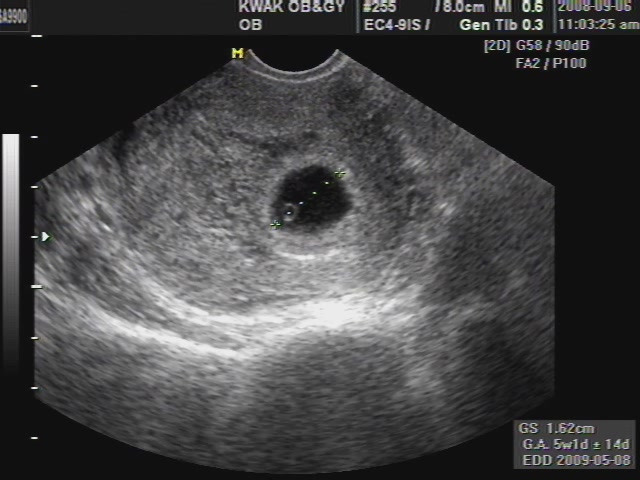

H:너무 먼 것 같아요. 지금 제게는 그냥 몸 건강하게 잘 뱃속에서 있다가 나오는 게 우선 순위이지, 앞으로 얘를 어떻게 키워야겠다까지는 아직 정립이 안된 상황이에요. 열 달 중에 이제 삼 개월밖에 안돼서 초음파를 찍어도 요만합니다.

사진출처 : 초음파 (https://www.google.co.kr/url?sa=i&rct=j&q=&esrc=s&source=images&cd=&cad=rja&uact=8&ved=0ahUKEwjXxviO3L7RAhVCn5QKHUjiAWcQjRwIBw&url=http%3A%2F%2Ft.jayoo.org%2F3&psig=AFQjCNFZaxWe_ptirL3-P6PpnOQj84atPg&ust=1484382896986855)